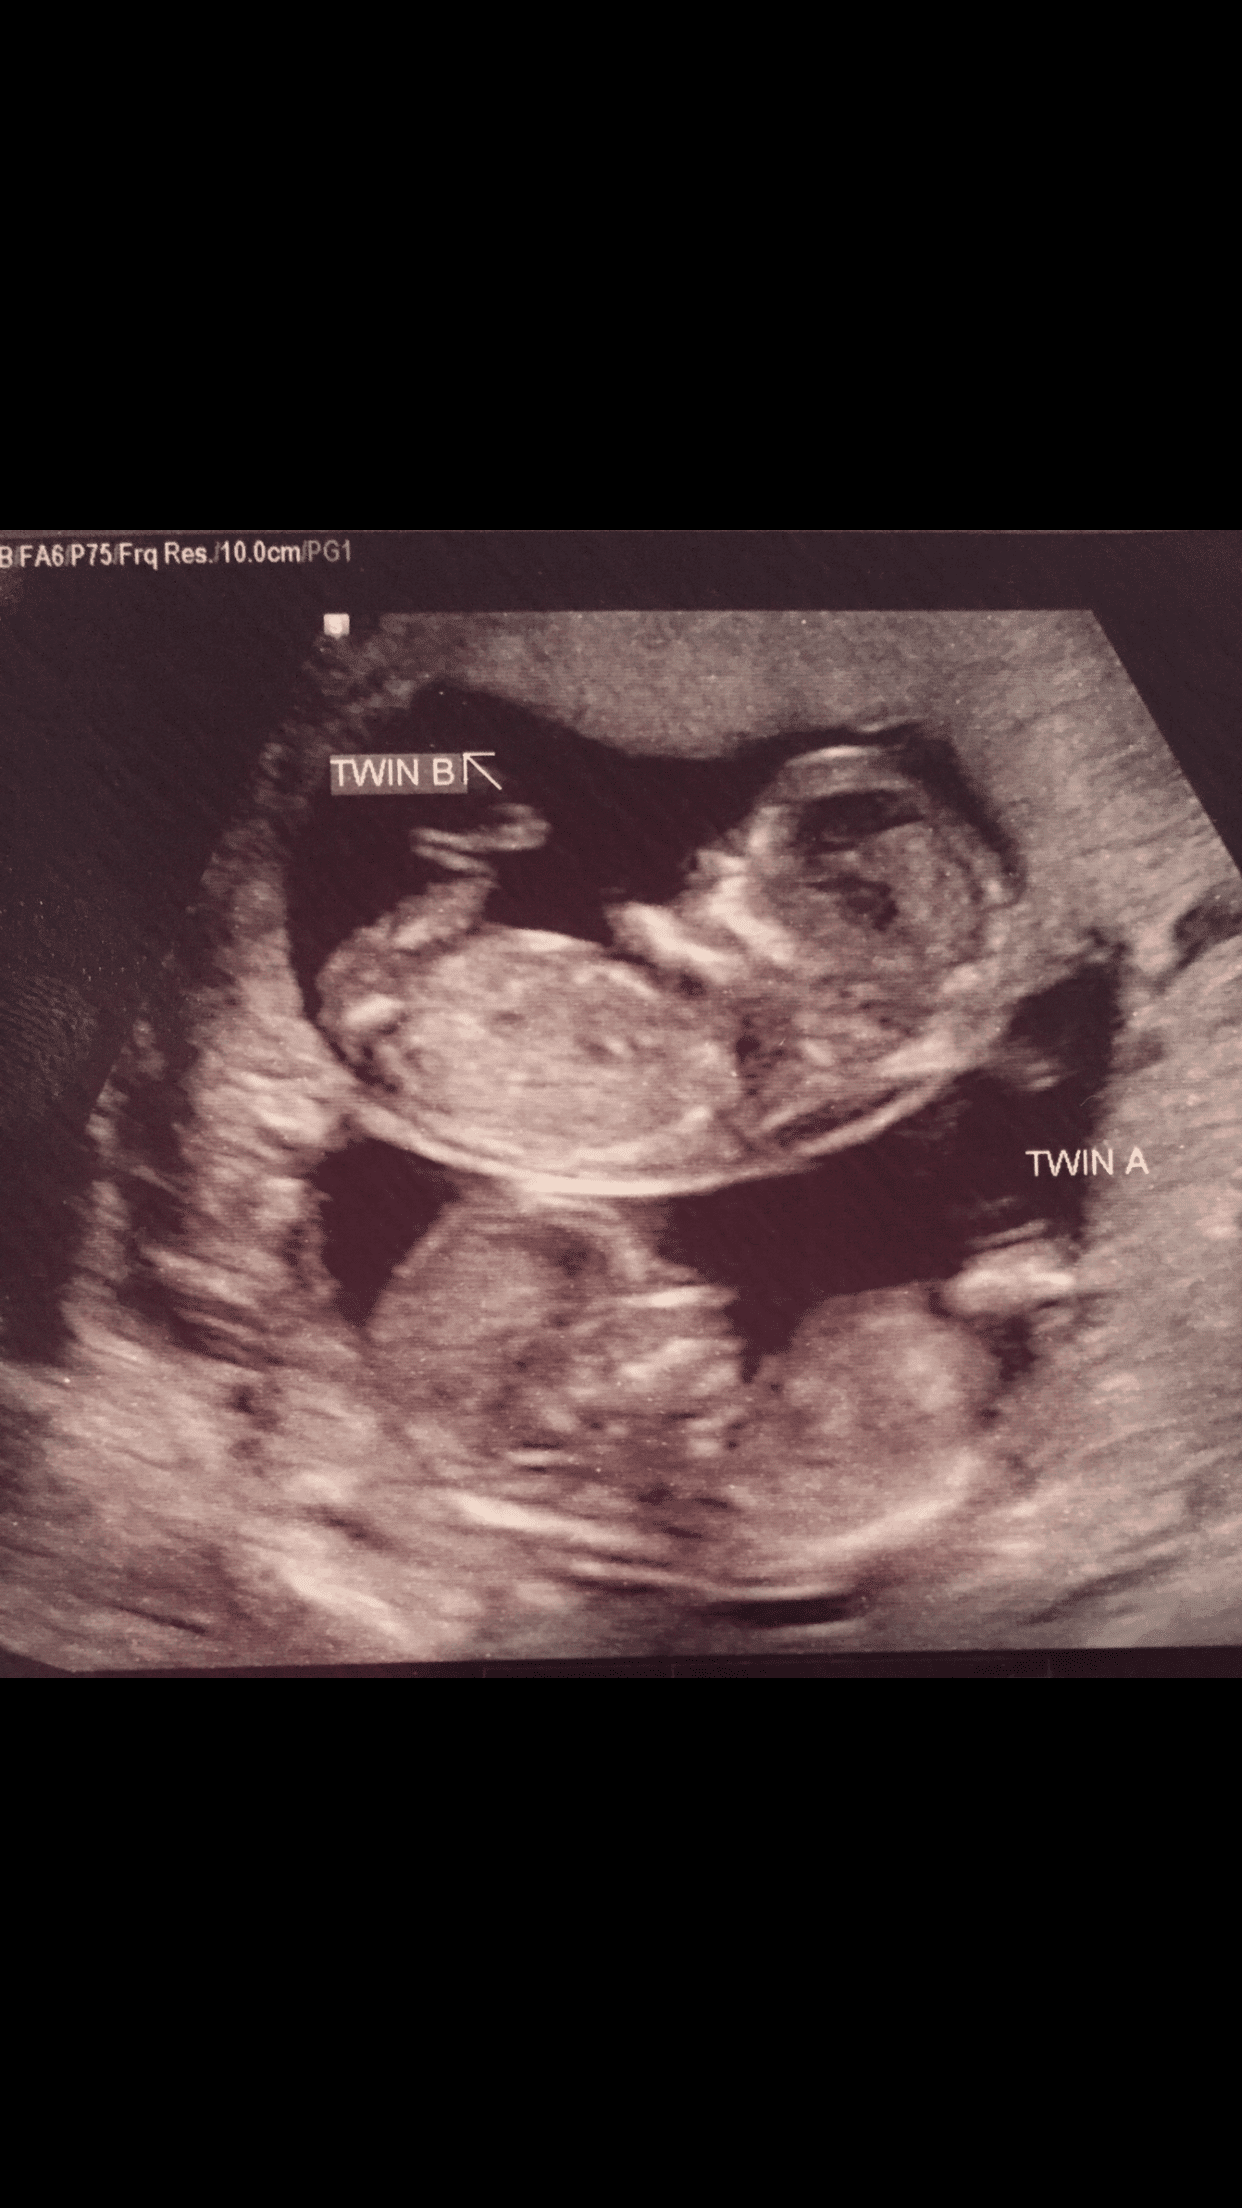

Ultrasound Photos at 12 Weeks Pregnant With Twins